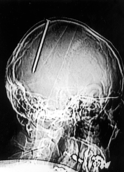

Un chiodo nel cervello. E non se ne era accorto!

Un uomo di 38 anni arriva in ospedale con un trauma cranico apparentemente minore dopo che un collega di lavoro ha fatto inavvertitamente cadere una sparachiodi sulla sua testa. L’uomo presenta una piccola ferita al cuoio capelluto, subito medicata, poi viene dimesso. Dieci giorni dopo ha un forte dolore e viene di nuovo visitato in ospedale. Sebbene non presenti segni di deficit neurologico, i medici fanno una TAC della testa…l’immagine mostra un chiodo di 7 cm infilato nell’emisfero cerebrale destro! Per fortuna dopo la rimozione del chiodo, l’uomo si è ripreso completamente (British Medical Journal Vol. 320 2000.)